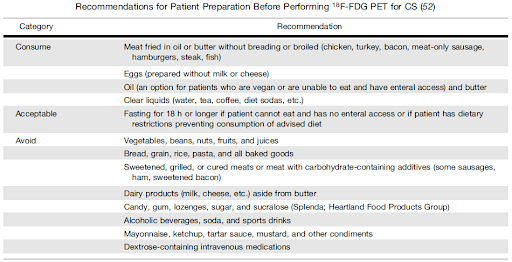

Preparing my patient for cardiac inflammation assessment:

- Purpose: Metabolic preparation prior to PET scan performed to identify inflammatory pathology of the heart, including cardiac sarcoidosis and cardiac infections, is very important. The aim of this diet is to suppress normal glucose usage by the heart muscle and force it to rather use energy from fat.

- Details: A high-fat, high-protein, very-low carbohydrate diet should be followed for ideally 3 days prior to the study followed by a prolonged period of not eating before the scan, for at least 12 hours but preferably 18 hours.

*Chareonthaitawee P, Beanlands RS, Chen W, et al. Joint SNMMI-ASNC Expert Consensus Document on the Role of 18F-FDG PET/CT in Cardiac Sarcoid Detection and Therapy Monitoring. J Nucl Med. 2017 Aug;58(8):1341-1353.